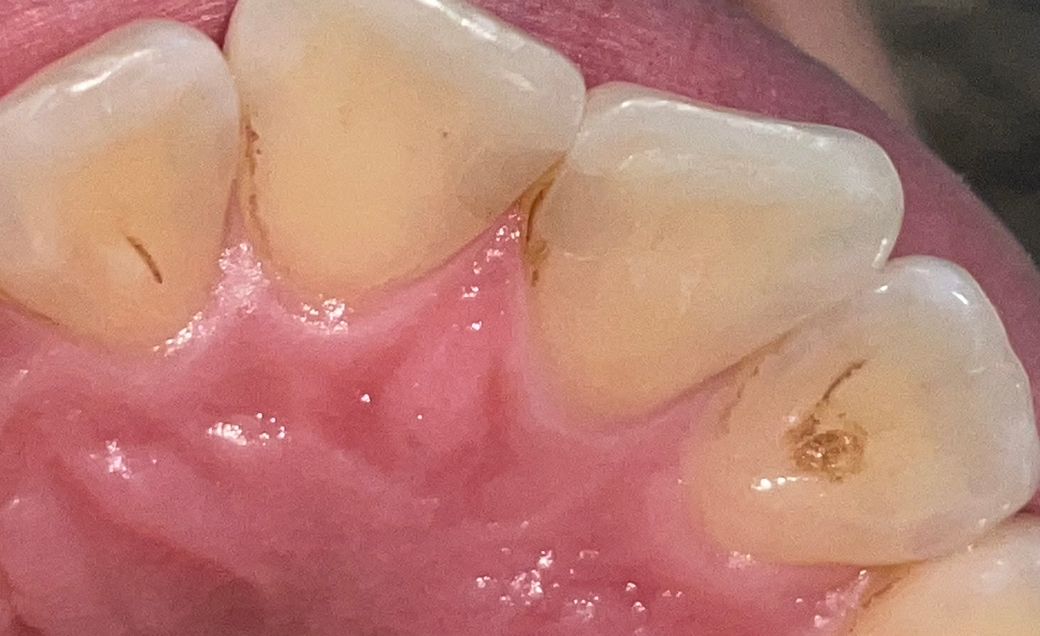

앞니 사이가 간질거리고 까만선이 보여요

요즘 앞니 사이가 간질거려서 거울을 봤는데 예전에 레진으로 때운 자리가 꺼만 때가 낀거 같네요 치석일까요? 스켕ㄹ링 한지는 네달정도 도ㅑㅆ슺니다

사진으로 봤을 경우에 충치를 치료한 부위에 레진으로 충전을 한 것으로 보입니다. 레진으로 충전한 부위 주변으로 충치가 생겼거나 접착이 약하게 되어 있다면 해당 부위가 불편할 수 있습니다. 이런 경우 충치를 다시 치료해줘야 되는 경우도 있으니 자세한 확인을 위해서 치과에서 진료를 받아보는 것이 좋습니다.

사진에 보이는건 착색이 된거 같습니다. 치과에 가셔서 스켈링을 받으시면 제거가 가능할꺼 같습니다.

네 레진 재료의 착색으로 보입니다 스케일링 주목적이 착색 제거가 아니기 때문에 그냥 지나쳤을 수도 있습니다 착색부위만 부분 스케일링 해달라고 하세요